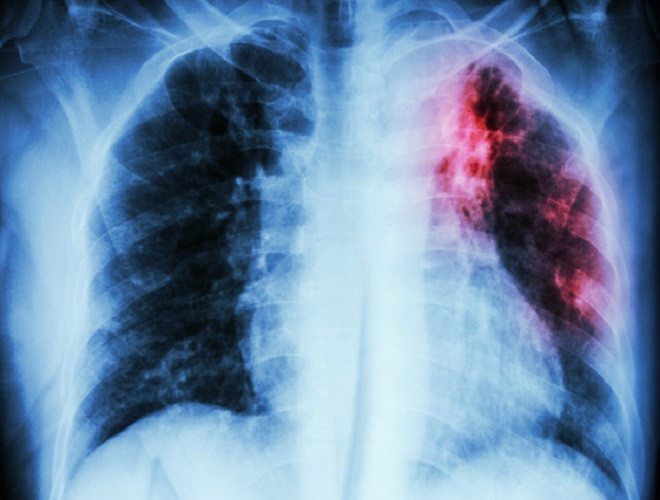

ANTD.VN - Vi khuẩn Whitmore "ăn thịt người" có thể xâm nhập qua vết thương trầy xước, làm tổ và "ăn mòn" cơ thể người. Bệnh tiến triển rất nhanh, có thể tử vong chỉ sau 48 giờ. Hiện chưa có vaccine và phương pháp phòng chữa bệnh đặc hiệu nên phòng ngừa bệnh là điều vô cùng cần thiết.